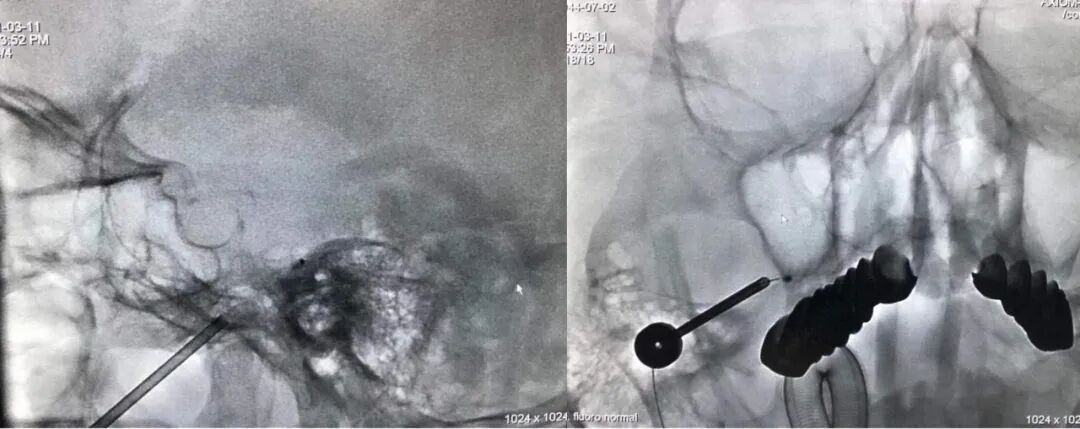

惠州三院神經(jīng)外科文世宏主任團(tuán)隊(duì)在麻醉科、介入室的配合下為周奶奶施行“三叉神經(jīng)痛半月節(jié)微球囊壓迫術(shù)”治療。手術(shù)十分成功,周奶奶終于擺脫了困擾他多年的三叉神經(jīng)痛,笑容重新布滿老人的面龐。

文世宏主任手術(shù)

微球囊壓迫技術(shù)是一種微創(chuàng)的治療技術(shù),該技術(shù)在C臂可視引導(dǎo)下進(jìn)行,醫(yī)生將穿刺針經(jīng)過疼痛面部的穿刺點(diǎn)進(jìn)行三叉神經(jīng)半月節(jié)穿刺,穿刺成功后,植入導(dǎo)管球囊,精準(zhǔn)定位三叉神經(jīng)半月節(jié),將球囊撐開呈“梨”形壓迫半月節(jié)3分鐘,術(shù)畢患者疼痛完全消失。而整個(gè)手術(shù)在全身麻醉下進(jìn)行,耗時(shí)約30分鐘左右,患者全程無痛苦。周奶奶手術(shù)后,臉上僅有針孔樣傷口,次日便出院回家!